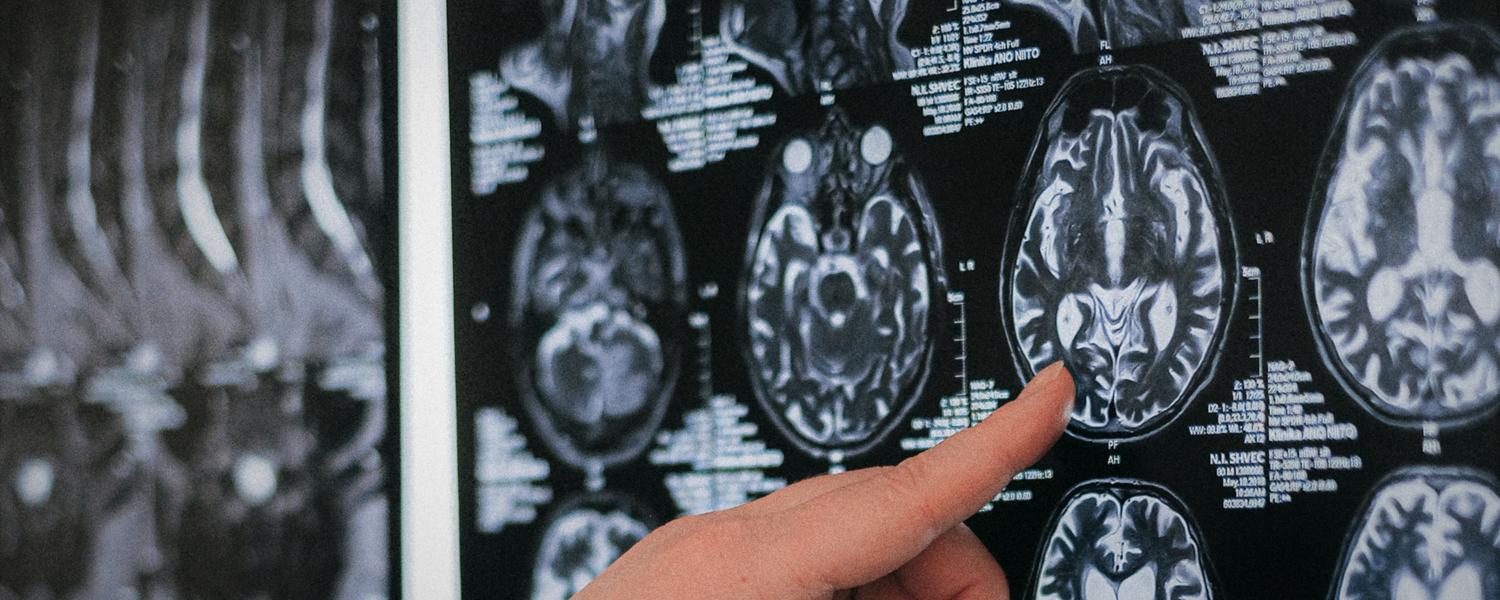

Healthy brain aging

Healthy brain aging leads to morphological changes in the cortical, subcortical and vascular structures of the brain. Several changes are also associated with neurological diseases such as Alzheimer’s diseases. Understanding better these changes is important to be able to differentiate pathological versus normal aging at an early stage.